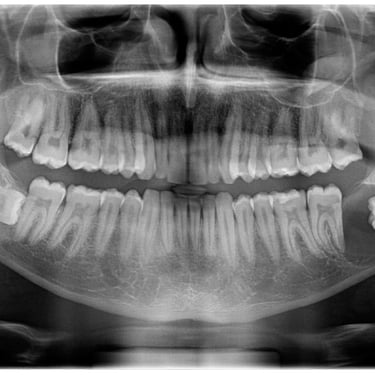

Extracción de Muelas del Juicio

La extracción de las muelas del juicio es un procedimiento quirúrgico para remover los terceros molares que pueden causar dolor, infección o daño a otros dientes debido a su posición o crecimiento anómalo.

Los pacientes pueden experimentar dolor, hinchazón y, en algunos casos, infección alrededor de estas muelas.

El tratamiento incluye la extracción quirúrgica para prevenir o resolver complicaciones.